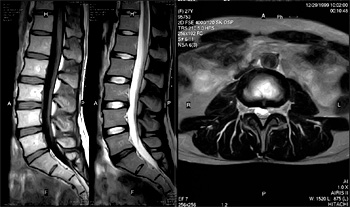

■ オープン型MRI装置

低音・開放・高速の最新の日立MRI装置を設置しております。

ワイドオープン型のシステムですので、圧迫感・閉塞感が少なく、小児やご高齢の方でも安心して検査が受けられます。

音が静かなMRI装置です。

画像は(株)日立メディコのHP(http://www.hitachi-medical.co.jp/product/mri/com/index.html)より引用